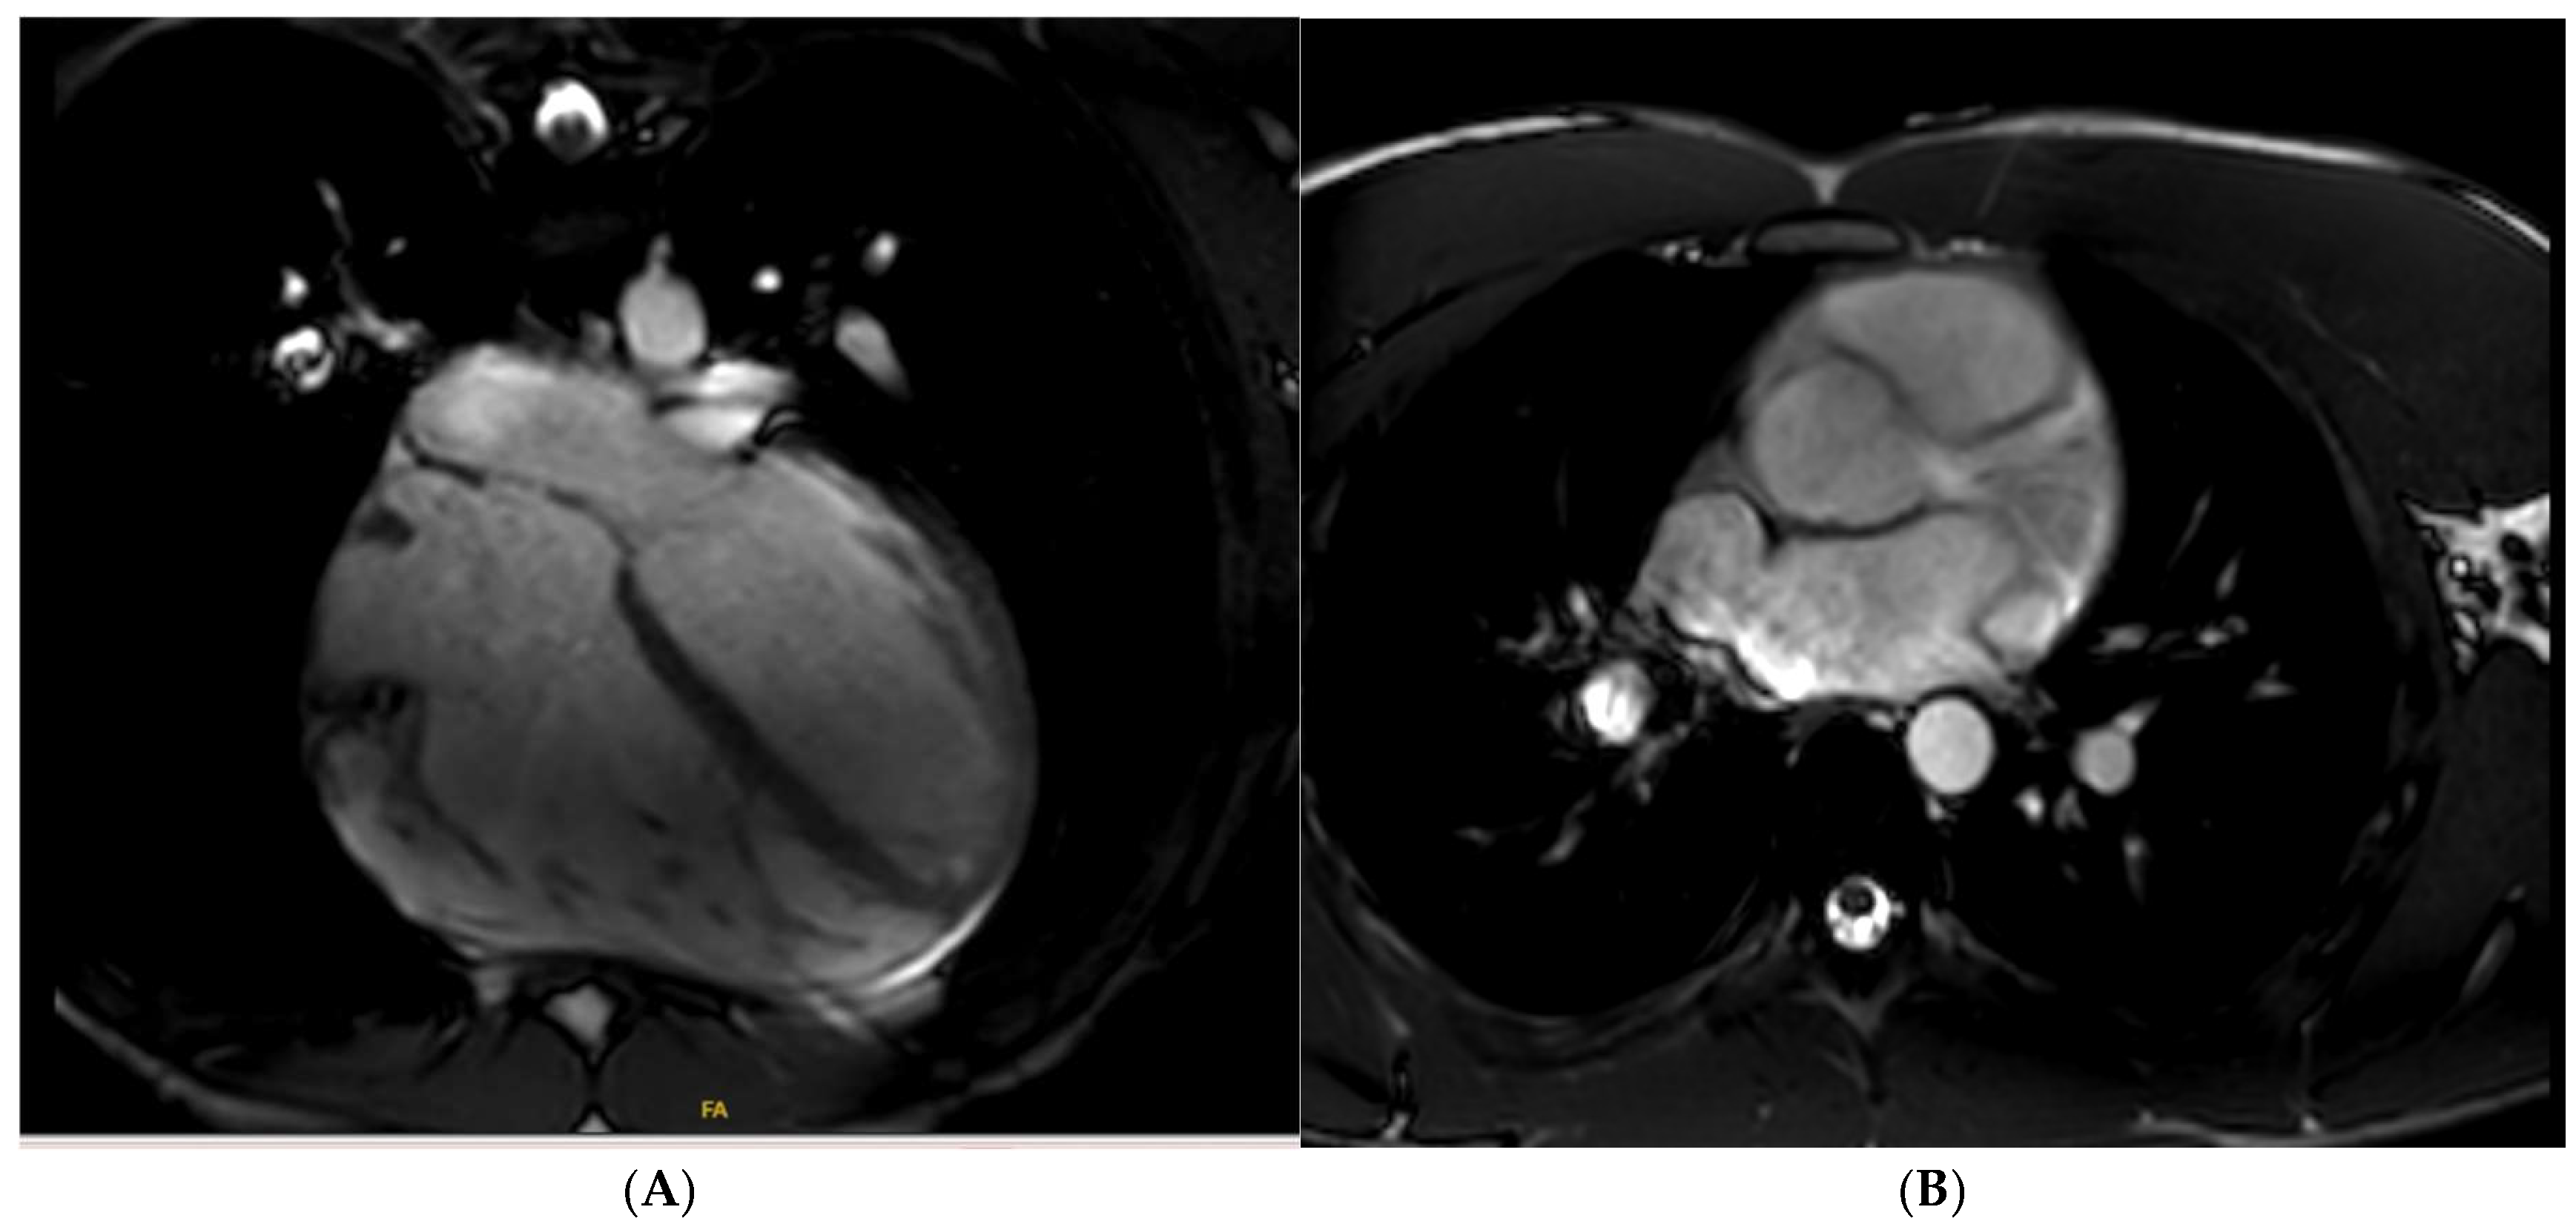

11. Left Ventricular Hypertrabeculation

19. Myocarditis